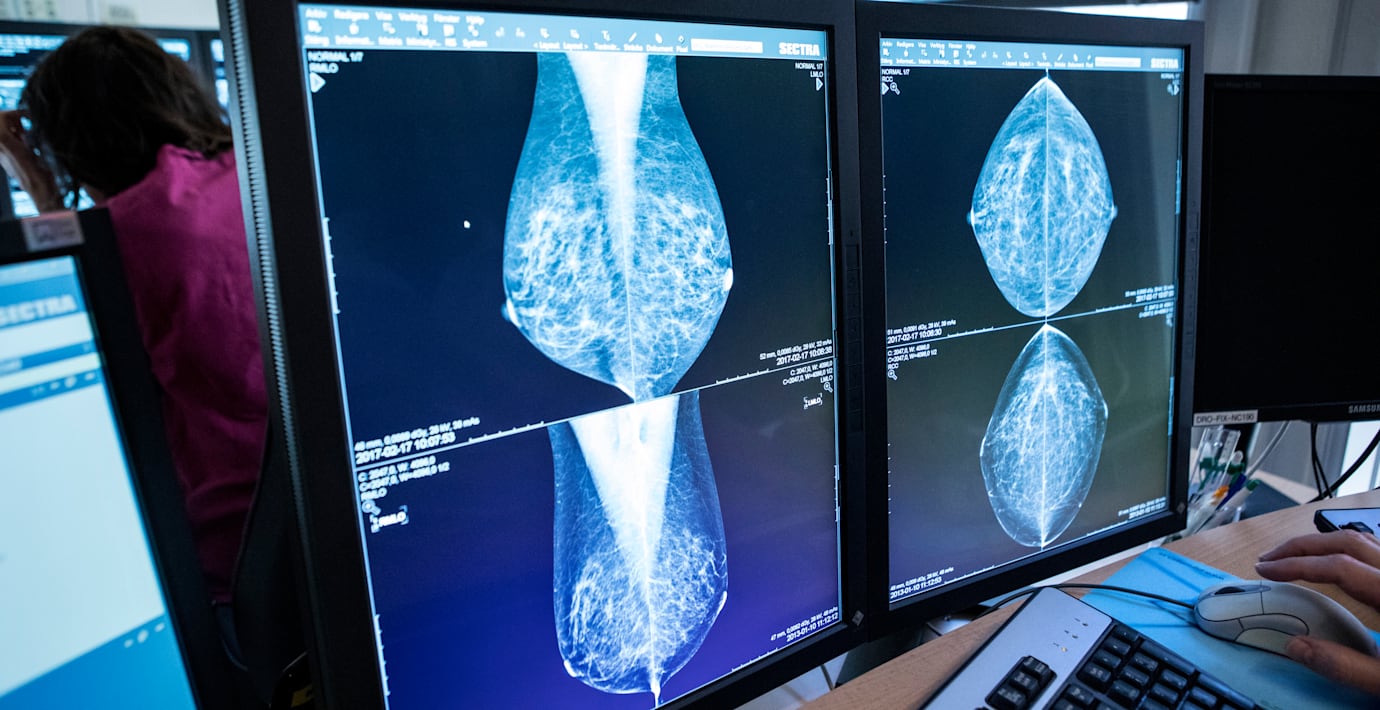

En läkare tittar på bröströntgenbilder, mammografibilder. (Christine Olsson/TT / TT Nyhetsbyrån)

Flera kvinnor som har screenats för bröstcancer har fått felaktiga svar i sina undersökningar. Missen beror på ett fel i en programvara som tolkar mammografibilder digitalt, vilket har inneburit att vissa patienter blivit friskförklarade för tidigt, rapporterar Dagens Medicin.

Företaget Sectra ligger bakom programvaran. I sin rapport till Läkemedelsverket beskrivs ett exempel med en kvinna som dog efter att ha friskförklarats, trots att hon senare diagnosticerades med bröstcancer.